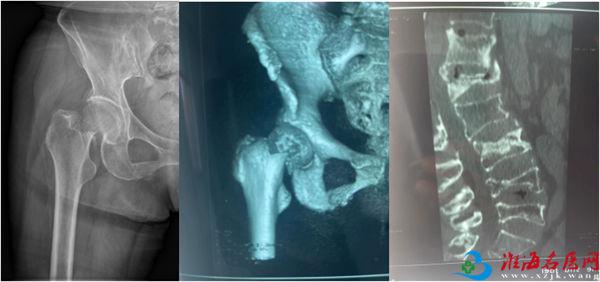

检查结果显示,谢某的身体状况良好,但骨折情况却相当严重。除了右侧股骨颈骨折伴有错位外,还有胸10、胸12、腰1、腰3和腰5等5个椎体的新鲜骨折。面对如此严重的多发骨折,传统的手术方式显然不是最佳选择,因为就算是年轻人也难以承受长时间的手术和麻醉。针对这一特殊情况,张镇提出了分多次进行微创手术的方案。这样既可以减少手术对患者身体的负担,又能达到最佳手术治疗效果。

按照术前计划,谢某首先接受了腰麻下的股骨颈骨折闭合复位空心钉内固定术。手术过程非常顺利,四十分钟便完成了。术后观察期间,医生为她进行了精心的后续治疗。病情稳定后,又为谢某做了两次腰椎骨折的微创手术。每次手术过程都是同样短暂,但效果极佳。局部麻醉的运用,谢某在手术过程中几乎感觉不到任何痛苦。

虽然术后的X光片看起来令人触目惊心,但实际上,这些复杂的手术都是通过微小的切口完成的。最大的伤口只有1公分大小,最多只需缝合一针。而背部的切口更是小得如同“小眼”一般,无需缝合和拆线。大约一周后,谢某就可以自行移除纱布了。